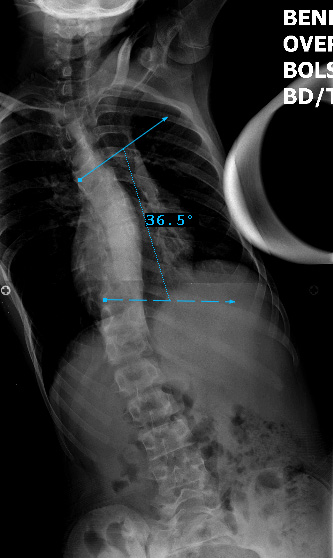

Preop LEFT Bend

Preop RIGHT Bend